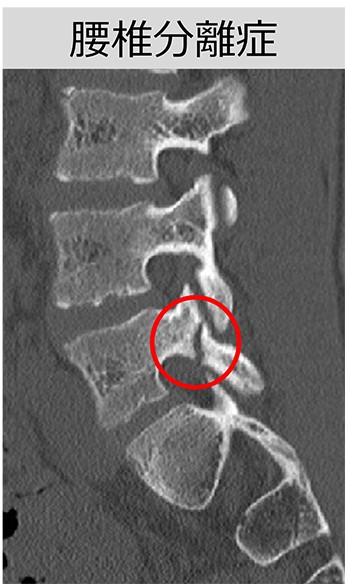

例えば、腰椎分離症。

ハムストリングスや股関節周りの柔軟性が低いと、腰椎の動きが制限されます

その状態でジャンプや背中を反らす動作で椎間間部に負荷がかかり、繰り返される事で疲労骨折の原因となります。